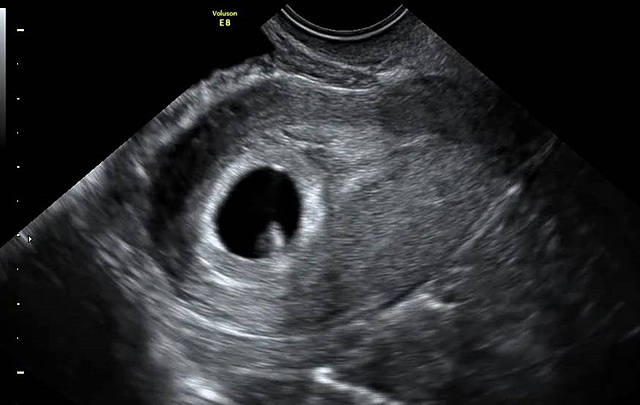

El latido del corazón del bebé se ve muy claro en la ecografía y su tubo neural ya empieza a cerrarse. De ahí la importancia de la suplementación de ácido fólico en el embarazo.El embrión ya mide entre 2 y 4 milímetros en la semana 6 de embarazo. Esta medida es la longitud desde la cabeza (el polo cefálico) hasta el final de la columna vertebral (el polo caudal). Por eso a esta medida se le llama LCC, Los ojos se están formando así como el primer vestigio cerebral